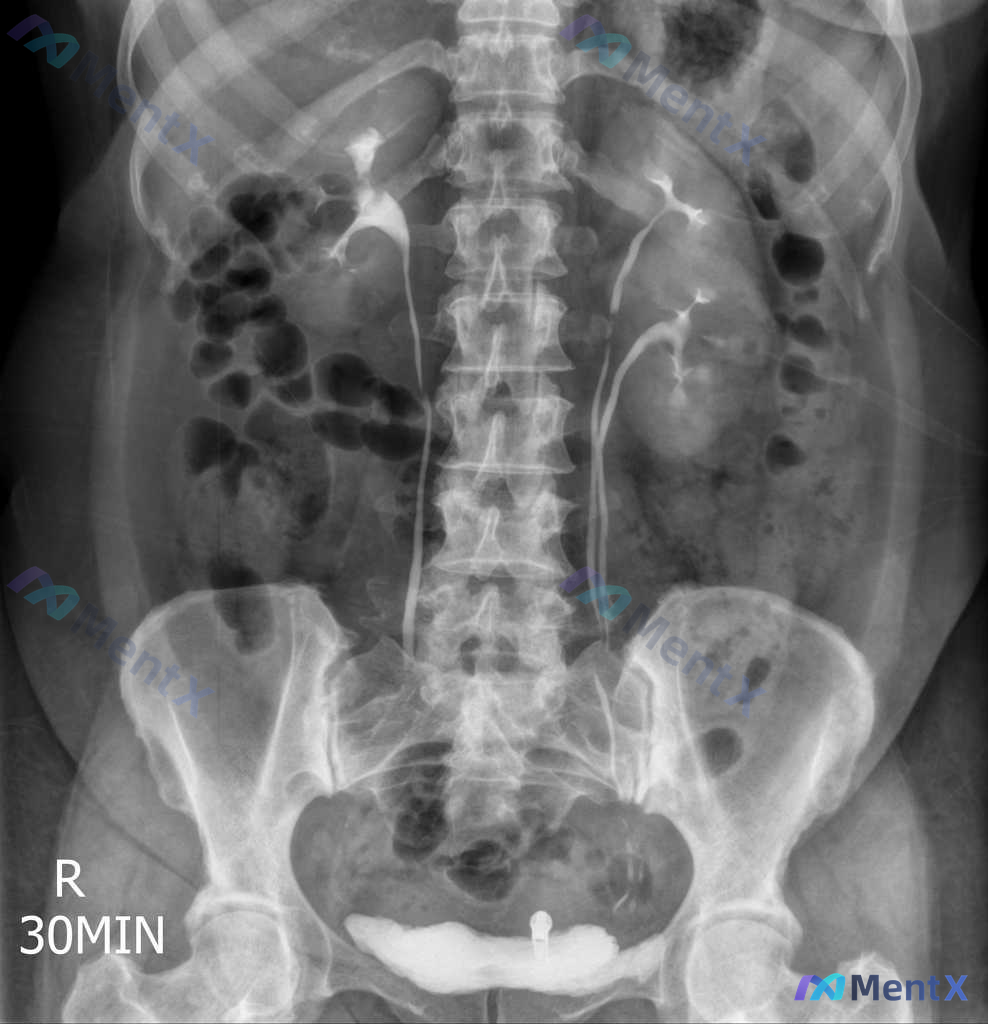

今天看到一个挺有意思的病例,整理了一下完整信息和思路,分享给大家讨论。 病例基本情况 - 患者:40岁女性 - 主诉:复发性尿路感染评估(过去1年4次UTI,需抗生素治疗) - 既往史/个人史:无其他异常,不吸烟酗酒,15年一夫一妻制,计算机程序员,与伴侣和两个孩子同住 - 生命体征:完全正常(T3...